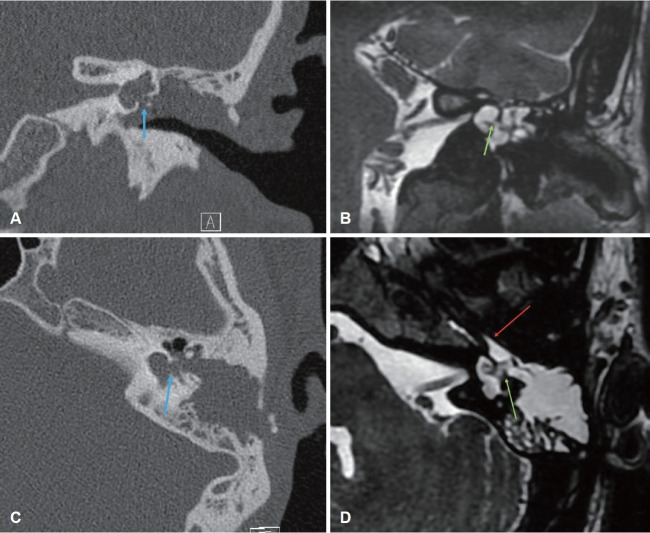

A 19-year-old male patient with a history of congenital left oval window defect has had recurrent admissions to a children's hospital for bacterial meningitis since the age of 7. Investigations revealed a left-sided type 1 incomplete partition deformity of the left ear with a congenital oval window defect, leading to communication between the cranium and the middle ear. The patient underwent a left canal wall down mastoidectomy and oval window defect repair, remaining well for 3 years. He experienced two more episodes of bacterial meningitis as he got older, prompting repeated exploratory tympanotomy and repair of the cerebrospinal fluid (CSF) leak after each episode. Recently, he was referred again for recurrent meningitis. Investigations showed a recurrent oval window defect. After undergoing left external ear canal transection, mastoid and middle ear obliteration, and left Eustachian tube obliteration, he remained well without further leaks or meningitis. Congenital oval window defect is rare and may present with recurrent bacterial meningitis secondary to spontaneous CSF leak via the oval window. Radiology plays a crucial role in identifying the source of the CSF leak, facilitating more precise preoperative counseling and surgical intervention.

{"title":"Recurrent Meningitis Following Previous Repair of Congenital Oval Window Defect.","authors":"Wan Qi Lim, Cherie Xinyi Seah, Kevin Chi Chuen Choy, Seng Beng Yeo, Jane Peiwen Lim","doi":"10.7874/jao.2024.00325","DOIUrl":null,"url":null,"abstract":"<p><p>A 19-year-old male patient with a history of congenital left oval window defect has had recurrent admissions to a children's hospital for bacterial meningitis since the age of 7. Investigations revealed a left-sided type 1 incomplete partition deformity of the left ear with a congenital oval window defect, leading to communication between the cranium and the middle ear. The patient underwent a left canal wall down mastoidectomy and oval window defect repair, remaining well for 3 years. He experienced two more episodes of bacterial meningitis as he got older, prompting repeated exploratory tympanotomy and repair of the cerebrospinal fluid (CSF) leak after each episode. Recently, he was referred again for recurrent meningitis. Investigations showed a recurrent oval window defect. After undergoing left external ear canal transection, mastoid and middle ear obliteration, and left Eustachian tube obliteration, he remained well without further leaks or meningitis. Congenital oval window defect is rare and may present with recurrent bacterial meningitis secondary to spontaneous CSF leak via the oval window. Radiology plays a crucial role in identifying the source of the CSF leak, facilitating more precise preoperative counseling and surgical intervention.</p>","PeriodicalId":44886,"journal":{"name":"Journal of Audiology and Otology","volume":"29 1","pages":"75-78"},"PeriodicalIF":1.4000,"publicationDate":"2025-01-01","publicationTypes":"Journal Article","fieldsOfStudy":null,"isOpenAccess":false,"openAccessPdf":"https://www.ncbi.nlm.nih.gov/pmc/articles/PMC11824527/pdf/","citationCount":"0","resultStr":null,"platform":"Semanticscholar","paperid":null,"PeriodicalName":"Journal of Audiology and Otology","FirstCategoryId":"1085","ListUrlMain":"https://doi.org/10.7874/jao.2024.00325","RegionNum":0,"RegionCategory":null,"ArticlePicture":[],"TitleCN":null,"AbstractTextCN":null,"PMCID":null,"EPubDate":"2025/1/20 0:00:00","PubModel":"Epub","JCR":"Q3","JCRName":"OTORHINOLARYNGOLOGY","Score":null,"Total":0}